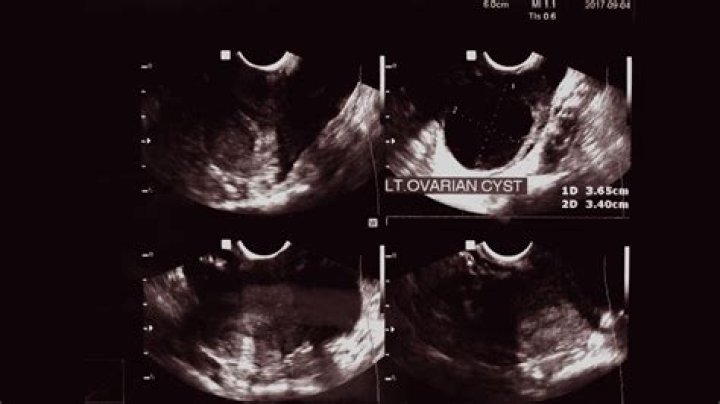

Can you see a cyst on an ultrasound?

Ultrasound imaging can help determine the composition of lump, distinguishing between a cyst and a tumour.

On ultrasound, they are usually smooth, round and black. Sometimes cysts do not have these typical features and they are difficult to distinguish from solid (non-fluid) lesions just by looking. These may need further testing to confirm they are cysts. Doctors sometimes describe these as “complex cysts”.

Vaginal ultrasound can help to show whether any cysts on your ovaries contain cancer or not. If a cyst has any solid areas it is more likely to be cancer. Sometimes, in women who are past their menopause, the ovaries do not show up on an ultrasound.

How can you tell the difference between a cyst and a tumor on an ultrasound?

For example, most waves pass through a fluid-filled cyst and send back very few or faint echoes, which look black on the display screen. On the other hand, waves will bounce off a solid tumor, creating a pattern of echoes that the computer will interpret as a lighter-colored image.